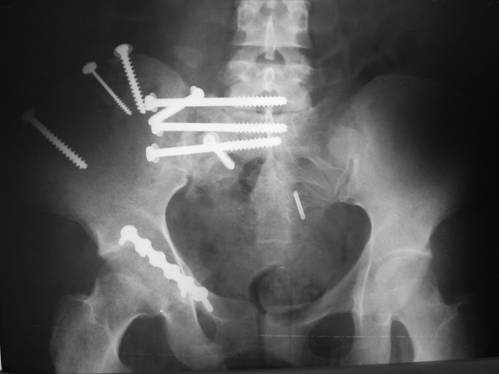

Пациентка С.26 лет. Травма за 6 месяцев до поступления

Укорочение правой нижней конечности до 10см

23.09.2003. Одновременный остеосинтез переднего и заднего тазовых полуколец

Результат через 10 дней